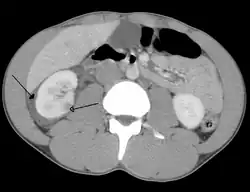

Abdominal trauma resulting in a right kidney contusion (open arrow) and blood surrounding the kidney (closed arrow) as seen on CT | |

Kidneys

The kidneys may also be injured; they are somewhat but not completely protected by the ribs.[6] Kidney lacerations and contusions may also occur.[13] Kidney injury, a common finding in children with blunt abdominal trauma, may be associated with bloody urine.[13] Kidney lacerations may be associated with urinoma or leakage of urine into the abdomen.[4] A shattered kidney is one with multiple lacerations and an associated fragmentation of the kidney tissue.[4]